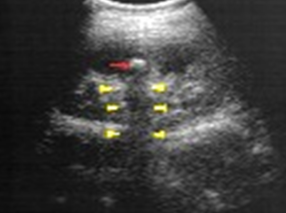

Kidney stone image

Hydronephrosis

Obstructive disease of the urinary system – dilatation of calyces and renal pelvis with urine. Long term can cause atrophy and loss of renal function.

Clinical indications for hydronephrosis

Most common cause is calculus/stone. Signs/Symptoms include flank pain and blood or pus in urine. May have abnormal labs if damage is present.

Treatment options for hydronephrosis

removal of stone

prognosis for hydronphrosis

excellent if caught prior to damage

hydronephrosis image